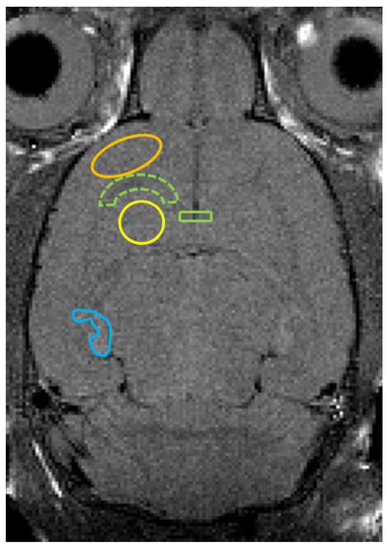

3.1. MRI Findings, T2 Value Measurements, and ADC Value Measurements